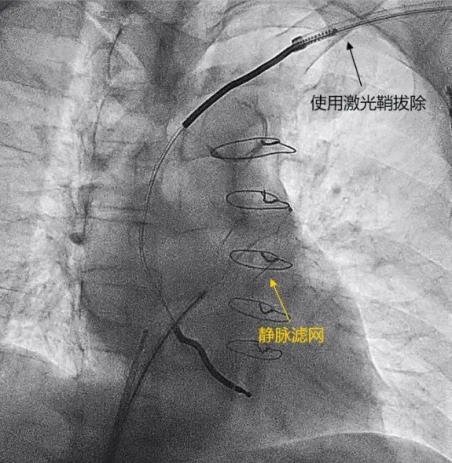

王大爷手术最大风险是拔除过程中电极上巨大赘生物脱落。经与血管外科、心外科专家多次沟通,最终决定将静脉滤器放置在肺动脉处,以阻挡手术过程中较大赘生物进入肺动脉、降低死亡风险,这在国内甚至国际上均属首创方案。

一切准备就绪后,王大爷接受了经静脉系统的拔除。李学斌教授团队将静脉滤器置于肺动脉,从锁骨下静脉途径使用锁定钢丝、激光鞘等多种工具,成功为王大爷拔除了心腔内的电极。术中患者血压、血氧平稳,没有出现急性肺栓塞及其他并发症。